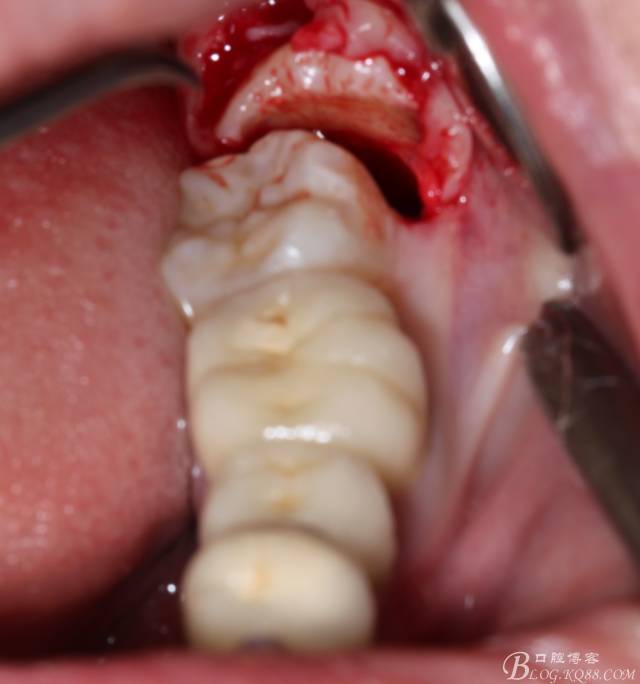

先分析智齒的情況,口內(nèi)直觀是半個(gè)牙尖都沒露出來,差一點(diǎn)就完全埋伏了。磨牙后墊的可操作面積中規(guī)中紀(jì),X全景片示三類阻生,根冠比例是1:1,非融合根,近中根壓下頜管。

640 (6).jpg